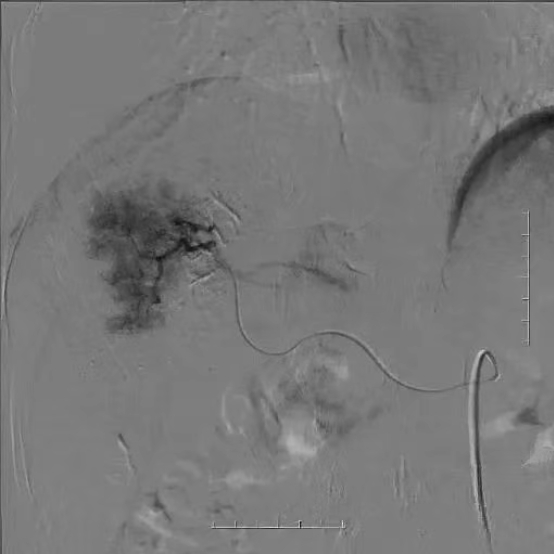

病例分享二

术中造影、栓塞、注射化疗药物

术后复查CT,可见瘤体内碘油沉积良好